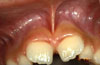

Es la especialidad de la Odontología que se encarga del tratamiento de la patología bucal en los pacientes en edad infantil y juvenil mientras presentan la dentición decidua (de leche), mixta o permanente. Los niños y los jóvenes deben seguir controles preventivos, al menos una vez al año, con el fin de diagnosticar de forma precoz los posibles problemas que puedan aparecer para efectuar inmediatamente los tratamientos lo menos agresivos posibles.

Los procedimientos que se hacen a estos pacientes son parecidos a los que se realizan a los pacientes adultos aunque en la dentición temporal y junto con las características psicológicas de los niños y jóvenes, requieren unas consideraciones específicas en relación con las técnicas y el manejo del paciente que es fundamental para poder ejecutar la opción terapéutica indicada sin producir dolor o malestar.